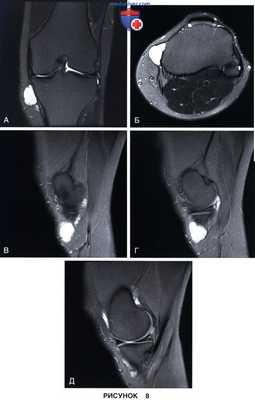

• Перименисковая киста (рис. 8)

6. МРТ позволяет оценить характер повреждения мениска, качество его ткани, диагностировать сопутствующие хондральные повреждения и/или другую патологию коленного сустава, а также наличие и структуру периартикулярных кистозных образований:

• Радиальный разрыв

• Горизонтальный разрыв по типу расслоения мениска:

- На рис. 3 представлены фронтальный (рис. 3, А) и сагиттальный (рис. 3, Б) МР-срезы с признаками горизонтального разрыва заднего рога внутреннего мениска

• Вертикальный продольный разрыв (рис. 4)

• Разрыв типа «клюв попугая»

• Разрыв типа «ручки лейки» с дислокацией:

- На МР-томограммах при разрыве мениска типа «ручки лейки» в сагиттальной проекции отмечается дефицит заднего рога мениска (рис. 5, А) и симптом «удвоения задней крестообразной связки» за счет смещения поврежденной части мениска в межмыщелковую вырезку (рис. 5, Б). На другом сагиттальном срезе также виден смещенный в межмыщелковую вырезку фрагмент мениска (рис. 5, В)

• Лоскутный разрыв с дислокацией

• Неполные разрывы в области верхней или нижней поверхности мениска (рис. 6 и 7)

• Комплексные или дегенеративные разрывы

• Подколенная киста.